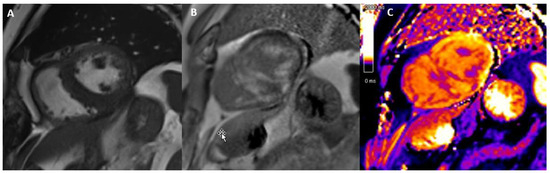

3.2. Acute Myocarditis

3.3. Chemotherapy-Induced Cardiotoxicity